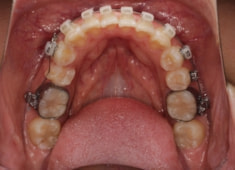

左上3番左下5番埋伏歯

治療法:フルパッシブブラケット:T21

治療開始時